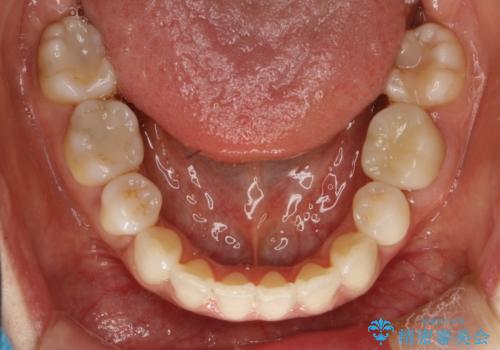

ハーフリンガル抜歯矯正 八重歯を改善する

シビアな八重歯がきれいに歯列にはいることにより、笑った時の印象などもかなり大きく変わります。